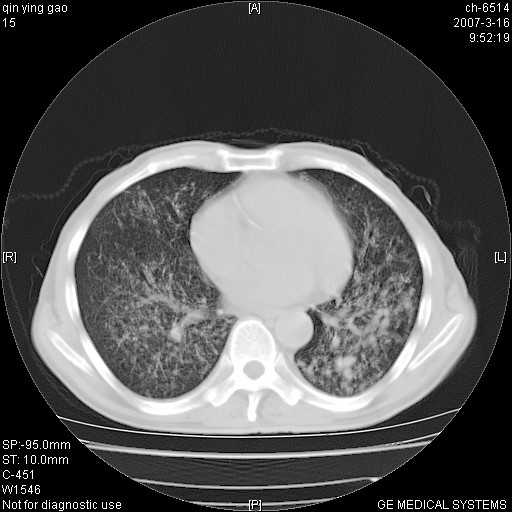

标题: CT7174:两肺弥漫性病变,请讨论

男,64岁.乏力2个月,畏寒、发热1月余。体重下降。血沉加快,白细胞不高。

两中上肺见有广泛新老不一的结节灶,并伴有纤维索条影,血沉加快,白细胞不高,首先考虑结核。

双肺以中上肺野为著斑片状.结节壮密度增高影 左上肺前段可见小类圆钙化灶 纵隔淋巴结无明显肿大

双肺可见大小不等结节状密度增高影,密度不均,分布不均(双肺上叶为著),亚急性血行播散性肺结核.

双肺以中上肺野为著斑片状.结节壮密度增高影,纵隔淋巴结无明显肿大。考虑:

(本例特征:以大小不等结节为主,主要分布在双上肺,并部分病灶融合成较大结节,期间搀杂诸多细小结节。从病灶特点与分布形式分析,更趋向于感染。)

男,64岁.乏力2个月,畏寒、发热1月余。体重下降。血沉加快,白细胞不高。 双肺可见大小不等结节状密度增高影,密度不均,分布不均(双肺上叶为著),亚急性血行播散性肺结核.

以双肺上叶为主的弥漫型斑片状密度增高影,边界欠清晰,其中伴有钙化灶,病人有发热史,首先考虑感染性病变:1特殊类型感染,2结核。建议治疗后随诊复查,除外肺泡癌

两中上肺见有广泛分布大小不一的结节灶及斑片状影,部分融合,双下肺未见异常密度影,纵隔无明显肿大淋巴结,血沉加快,白细胞不高,首先考虑结核。 建议结合ppd检查或痰培养排除其他非特异性炎症。

中上肺野密布棉团状影,以胸膜下区为界,边缘模糊,可能是小叶或腺泡渗出及实变。全肺野弥漫分布网线样影及细小粟粒样影,可能是细支气管炎及间质内炎症。综合分析应首先考虑气道播散性感染,而肺内多处斑点性钙化,强烈提示陈旧结核复发并支气管播散。建议详细讯问病史

病变以两肺上野为著,部分病灶有钙化,纵隔窗显示病灶有新老不一,这个首先和结核脱不了干系,还有部分病灶有融洽的倾向,肿瘤也不能完全排出